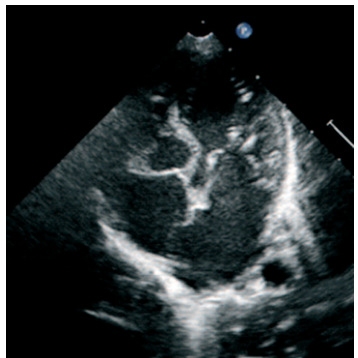

Isquemia miocárdica masiva tras fístula de Blalock-Taussig

IMÁGENES EN CARDIOLOGÍA